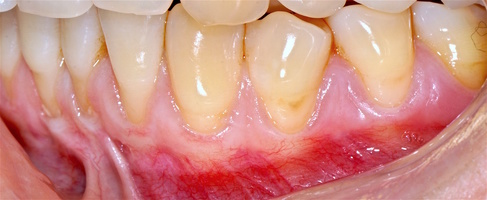

В марте 2017 года в клинику обратилась пациентка Ч., 28 лет (табл. 1) без вредных привычек, с положительным социальным статусом, астенического телосложения. С жалобами на тотальное обнажение корней зубов с повышением чувствительности от термических раздражителей, эстетические дефекты, абразии твердых тканей зубов.

Исходный объем мягкотканного комплекса атрофичен, тонкий биотип десны. Мелкое преддверие полости рта на нижней челюсти в переднем отделе, от 44-го до 34-го зубов высокое прикрепление слизисто-мышечных тяжей.

Форма зубной дуги — эллипсовидная, с незначительным сужением в области премоляров на верхней челюсти; во фронтальных участках верхней и нижней челюстей окклюзия в протруссии. Зубы крупные, вытянутые по форме. Межальвеолярный контакт в норме, прикус ортогнатический. Гигиенические индексы: IG–1,2(HYG),PI—6,GI—0,PBI—0.

В области от 1.6 до 2.6 и от 3.6 до 4.6 все зубы имеют некариозные поражения разной степени, такие как эрозии эмали и клиновидные дефекты, вовлекающие в процесс ткани эмали и дентина. Подвижности зубов не выявлено (рис. 1а-е) [9].

При анализе и описании компьютерной конусно-лучевой томографии (рис. 2а-г) была выявлена генерализованная первичная дегисценция вестибулярной пластинки кости от 1/2 до 3/4 длины корней зубов, зубной ряд целостный, все зубы витальны, кариозных поражений нет. Тип кости 1-2 (Lechkolm и Zarb, 1983), первичная дегисценция вестибулярной костной пластинки превышает пределы возрастной атрофии.